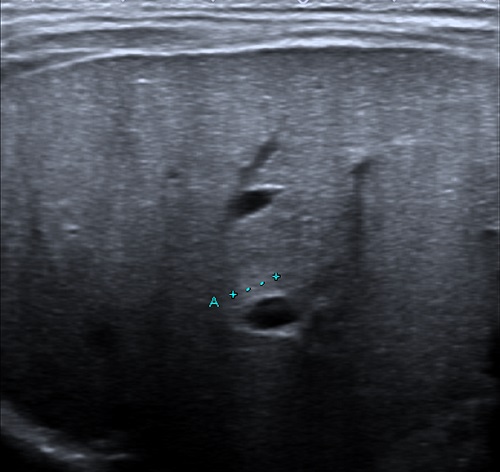

Mantiene un seguimiento conjunto por Neonatología y AP por persistencia de vómitos, irritabilidad y fallo de medro a pesar de una adecuada técnica de LM. A los dos meses, presenta ictericia, hepatomegalia y deposiciones hipocólicas, sin coluria. En la analítica sanguínea se evidencian signos de colestasis, con bilirrubina directa elevada e hipertransaminasemia, solicitándose nueva ecografía abdominal con hallazgos de AVB (Figura 1).

Figura 1. Signo del cordón triangular: hallazgo sugestivo de AVB